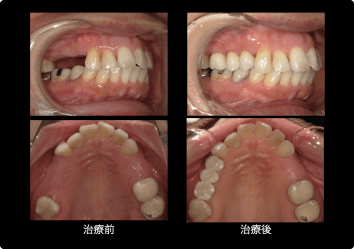

部分入れ歯が噛めない、違和感が強かった方のインプラント治療

BEFORE

AFTER

症例概要

年代・性別

50歳代 女性

主訴

入れ歯が噛めない

治療内容

上顎4番・6番インプラント、上5番 セラミッククラウン(デジタル)

治療期間

3ヶ月

治療のリスク

インプラント周囲炎のリスクがあるため、メンテナンスに来ていただきます。

治療費用

924,000円(税込)